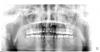

Bier Опубликовано 14 июля, 2008 Поделиться Опубликовано 14 июля, 2008 по снимку совершенно нормальный уровень костной ткани, просто корни зубов короткие. Кости больше не станет, разве что станет более плотной. З.Ы. удалил ваше сообщение т.к. Korabahtoff - прав. Ссылка на комментарий